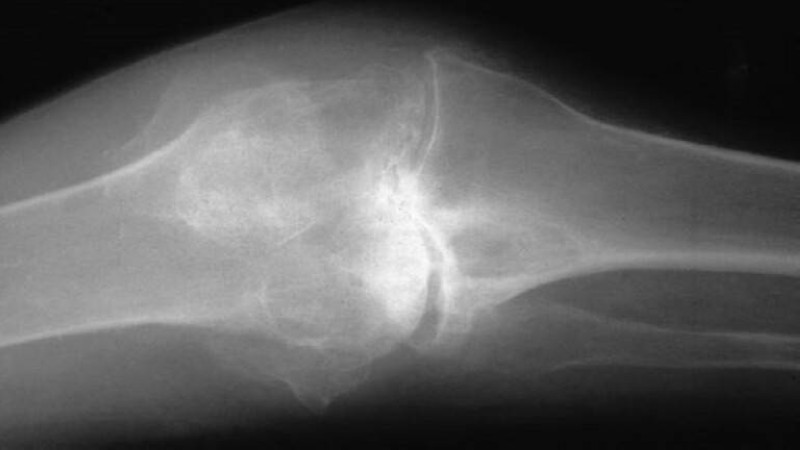

أكدت دراسة أجراها علماء من جامعة كارول نسكا الطبية السويدية ونشرتها مجلة PNAS، أن التهاب المفاصل الروماتيدي منتشرا جداً، والأشخاص المصابون به يعانون طوال حياتهم من الألم الدائمة.